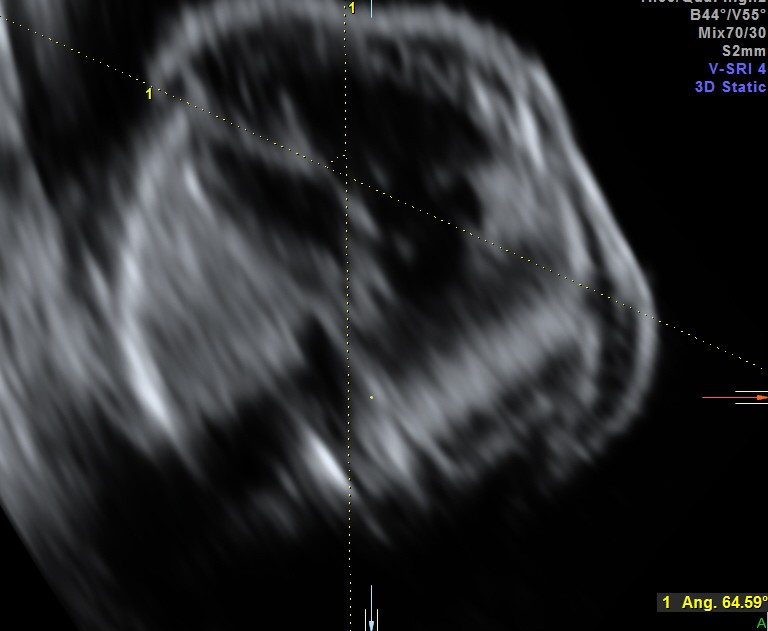

the following 3 D reconstructed image shows the parallel flow of the great arteries